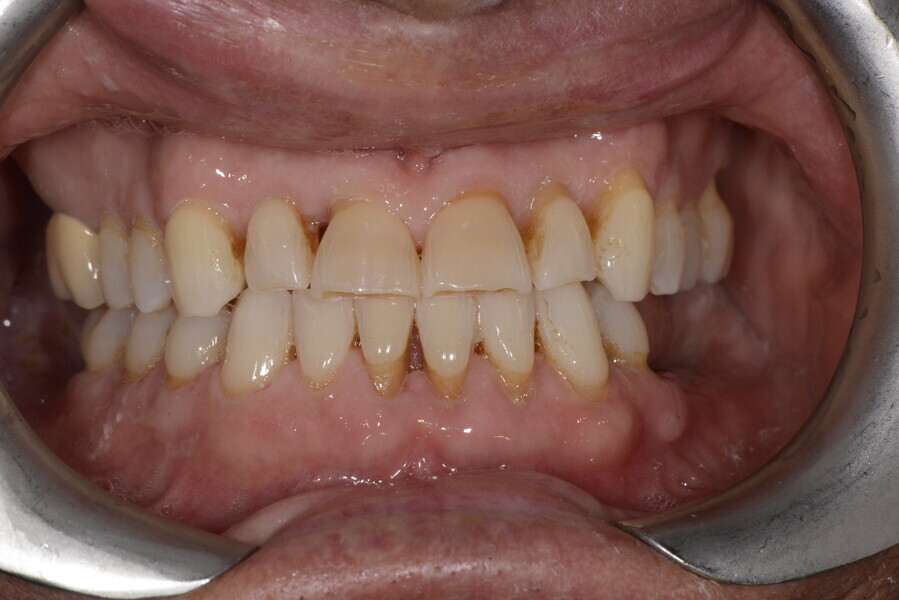

After the first phase of aligner treatment, we had achieved better inter-arch coherence, better maxillary arch expansion, and some space for improving the anterior tooth proportions restoratively (Fig. 19). We then temporarily restored the anterior teeth directly with composite, closing the spaces, improving the tooth proportions and further increasing the maxillary arch expansion (Fig. 20). We used restorative arch expansion to reduce the orthodontic destabilisation of the teeth to achieve the correct inter-arch coherence and retain the teeth in the cortical bone.38 A refinement aligner phase was undertaken to improve the final alignment of the gingival zenith and to improve the inter-arch coherence (Fig. 21). The periods of the first orthodontic phase and of the refinement were used to augment the mandibular and maxillary bone and to place the implants (Fig. 22). At the end of the orthodontic treatment, the case was finalised with ceramic veneers in the anterior area and temporary restorations on the implants in the posterior area (Figs. 23–26).

The provisional phase of about four months was important to allow the peri-implant tissue to mature and to teach the patient to chew correctly with chewing gum, cotton rolls and silicone masticatory sticks. This is fundamental training for the patient to achieve the correct alternating unilateral masticatory cycle needed to obtain the ideal rehabilitation of the masticatory system. We wanted the patient to achieve ideal masticatory and swallowing function. After sufficient rehabilitation time, we finalised the case with posterior zirconia crowns screwed on to the implants (Fig. 27).26

Our ideal final rehabilitation goals were:

• posterior stability;

• inter-arch coherence and U-shaped arches;

• anterior freedom during mastication;

• minimum disclusion vertical dimension;

• alternating unilateral masticatory cycle;

• physiological swallowing and high tongue posture against the palate; and

• mandibular disclusion advancing the mandible freely.

For maintenance purposes, after prosthetic finalisation, the patient was to carry on with the Froggymouth therapy and to use the Ri.P.A.Ra. for physiotherapeutic exercises and mastication training (Fig. 28). It was strongly recommended that the patient wear a mandibular occlusal splint during sleep. This occlusal splint was designed with disclusion guides to advance the mandible and ensure balanced contralateral support (Fig. 29).11, 39 We achieved an aesthetic appearance with adequate inter-arch coherence and a better cephalometric result (Figs. 30 & 31).